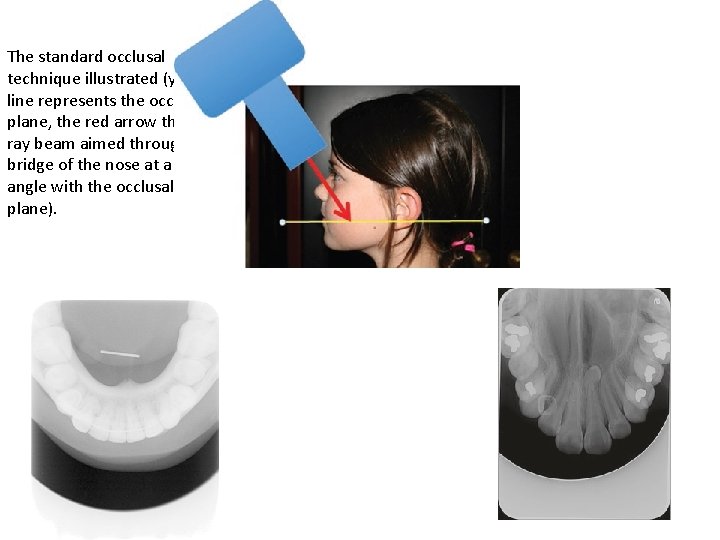

The standard occlusal technique illustrated (yellow line represents the occlusal plane, the red arrow the Xray beam aimed through the bridge of the nose at a 65° angle with the occlusal plane).